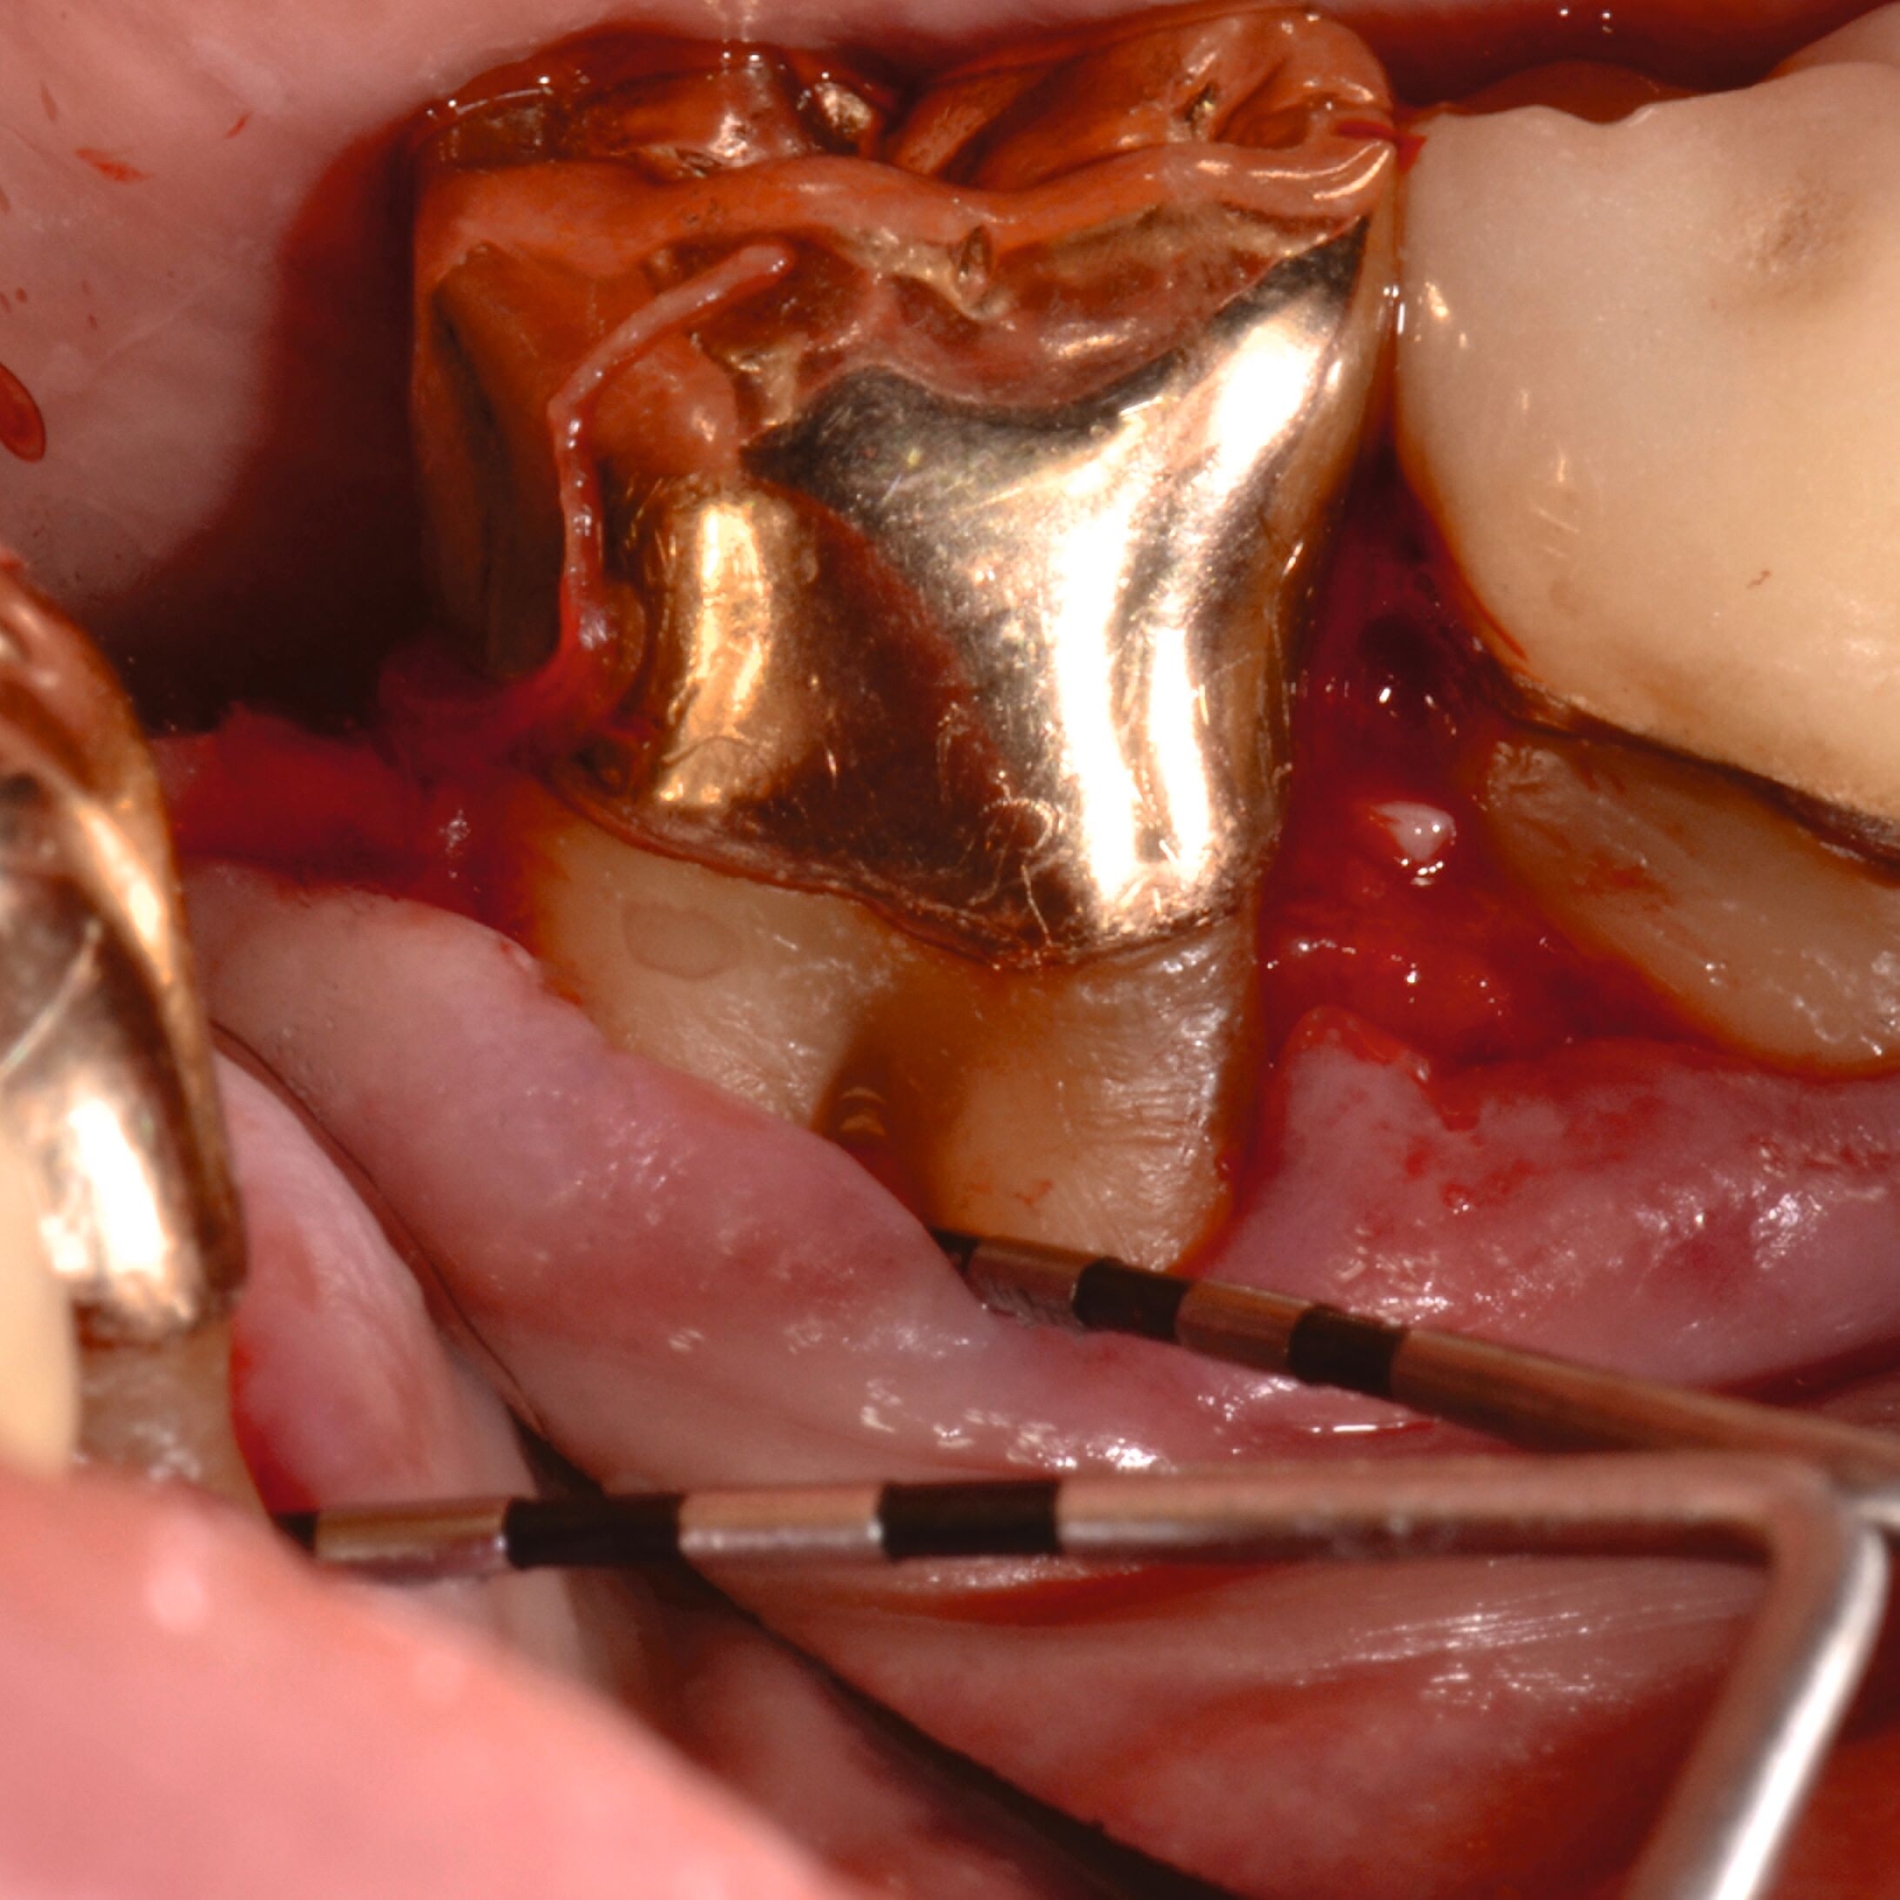

3. Regenerative Parodontalchirurgie

Ziel ist es, einen ausreichenden Zugang zum Defekt für eine sorgfältige Instrumentierung und die Applikation des Biomaterials zu erhalten. Bei isolierten Defekten können vertikale Entlastungsinzisionen verwendet werden. Alternativ kann der Lappen nach lateral zu den benachbarten Zähnen erweitert werden. Keratinisiertes Gewebe sollte durch intrasulkuläre Inzision und die Anhebung eines Mukoperiostlappens erhalten werden. Das Granulationsgewebe wird entfernt und die freiliegenden Wurzeloberflächen werden sorgfältig mit Handinstrumenten, oszillierenden Scalern (optional mit fein diamantierten Spitzen) oder rotierenden Instrumenten gereinigt. Wurzelanomalien wie Schmelzvorsprünge/-perlen sollten entfernt werden. Wenn EMD Teil der Regenerationsstrategie ist, wird es in der Regel nach einer zweiminütigen Wurzelkonditionierung mit Ethylendiamintetraacetat (EDTA) und Spülung mit steriler Kochsalzlösung angewendet. Anschließend kann ein Knochentransplantat/-ersatzmaterial verwendet werden, um den Furkationsdefekt aufzufüllen.

Alternativ kann eine GTR-Barrieremembran mit oder ohne zusätzlichen Defektfüller appliziert werden. Die Barrieremembran wird mit einer resorbierbaren Umschlingungsnaht befestigt, um den Furkationseingang abzudecken und die Wund- und Koagulumstabilisierung zu fördern. Um eine vollständige Abdeckung der Barriere zu ermöglichen, kann das Periost durchtrennt werden, um den Lappen leicht koronal zu verschieben. Der Lappen wird mit einer Umschlingungsnaht und Einzelknopfnähten über den vertikalen Entlastungsinzisionen oder mit interdentalen Nähten im Fall eines lateral extendierten Lappens in einer koronalen Position gesichert. Der Patient wird angewiesen, für einen Zeitraum von bis zu vier Wochen auf die mechanische Plaqueentfernung im Operationsgebiet zu verzichten. Während dieser Zeit werden Chlorhexidin-Spülungen oder -Gel verwendet. Der Patient kehrt zur Kontrolle der Wundheilung nach ein und zwei Wochen zurück, wenn die Nähte entfernt werden. Die Interdentalhygiene und die mechanische Plaqueentfernung werden nach vier Wochen wieder aufgenommen. Zudem wird ein individuelles Recallprogramm zur unterstützenden Parodontitistherapie (UPT) festgelegt.